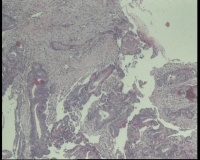

性别

女

年龄

43岁

临床诊断

结肠CA

一般病史

进镜达横结肠近肝曲,见不规则增生性肿物,环周生长,表面充血糜烂,触之易出血,肠腔狭窄,镜身无法通过

标本名称

肠镜活检

大体所见

肠镜活检4块

镜下腺体异型小,纤维间质反应,能直接报结肠腺癌吗?

可一类报告报:管状绒毛状腺癌

高-中分化腺癌。